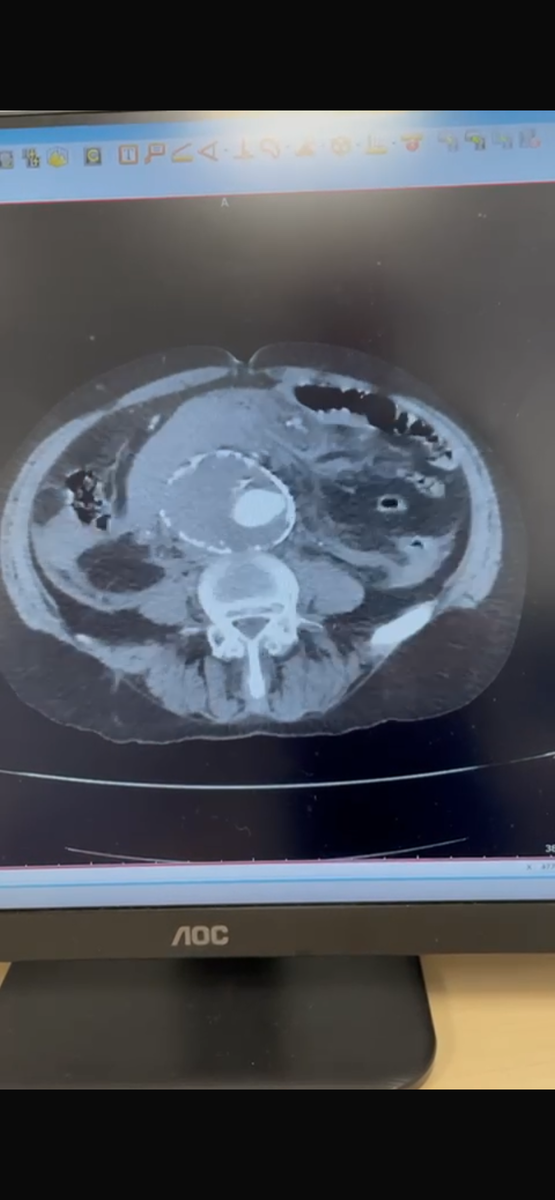

Что делать, если у вас обнаружили аневризму брюшного отдела аорты?

Аневризма представляет собой расширение стенки аорты, которое может привести к ее разрыву и, как следствие, к жизни угрожающим состояниям. Очень часто это случайная находка.

• В-третьих, важно проходить регулярные медицинские обследования. Врач может назначить МСКТ для контроля за изменениями в размере аневризмы и для оценки состояния кровеносных сосудов.